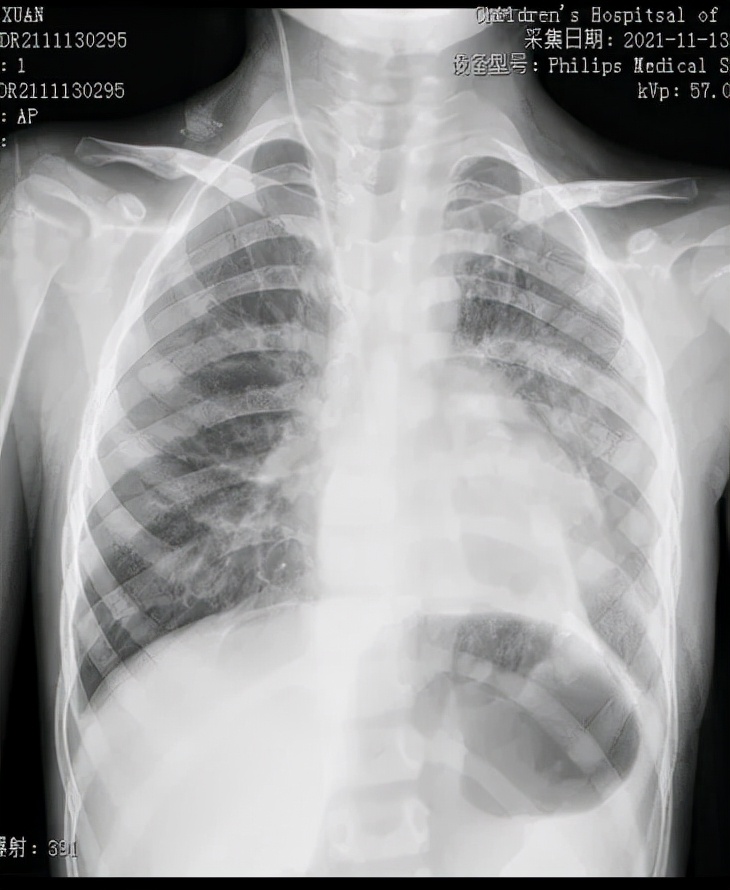

术后

在胸腔镜视野下,可看到楠楠的左侧胸腔内充满了胃和肠子,而左肺则受压变小,医生们帮助腹腔各脏器回到它们原本的位置,紧接着修补了缺损的膈肌,最后让受压的左肺重新膨开了。

胸腔镜手术的顺利完成大大减少了对患儿创伤,为预后打下了良好的基础。